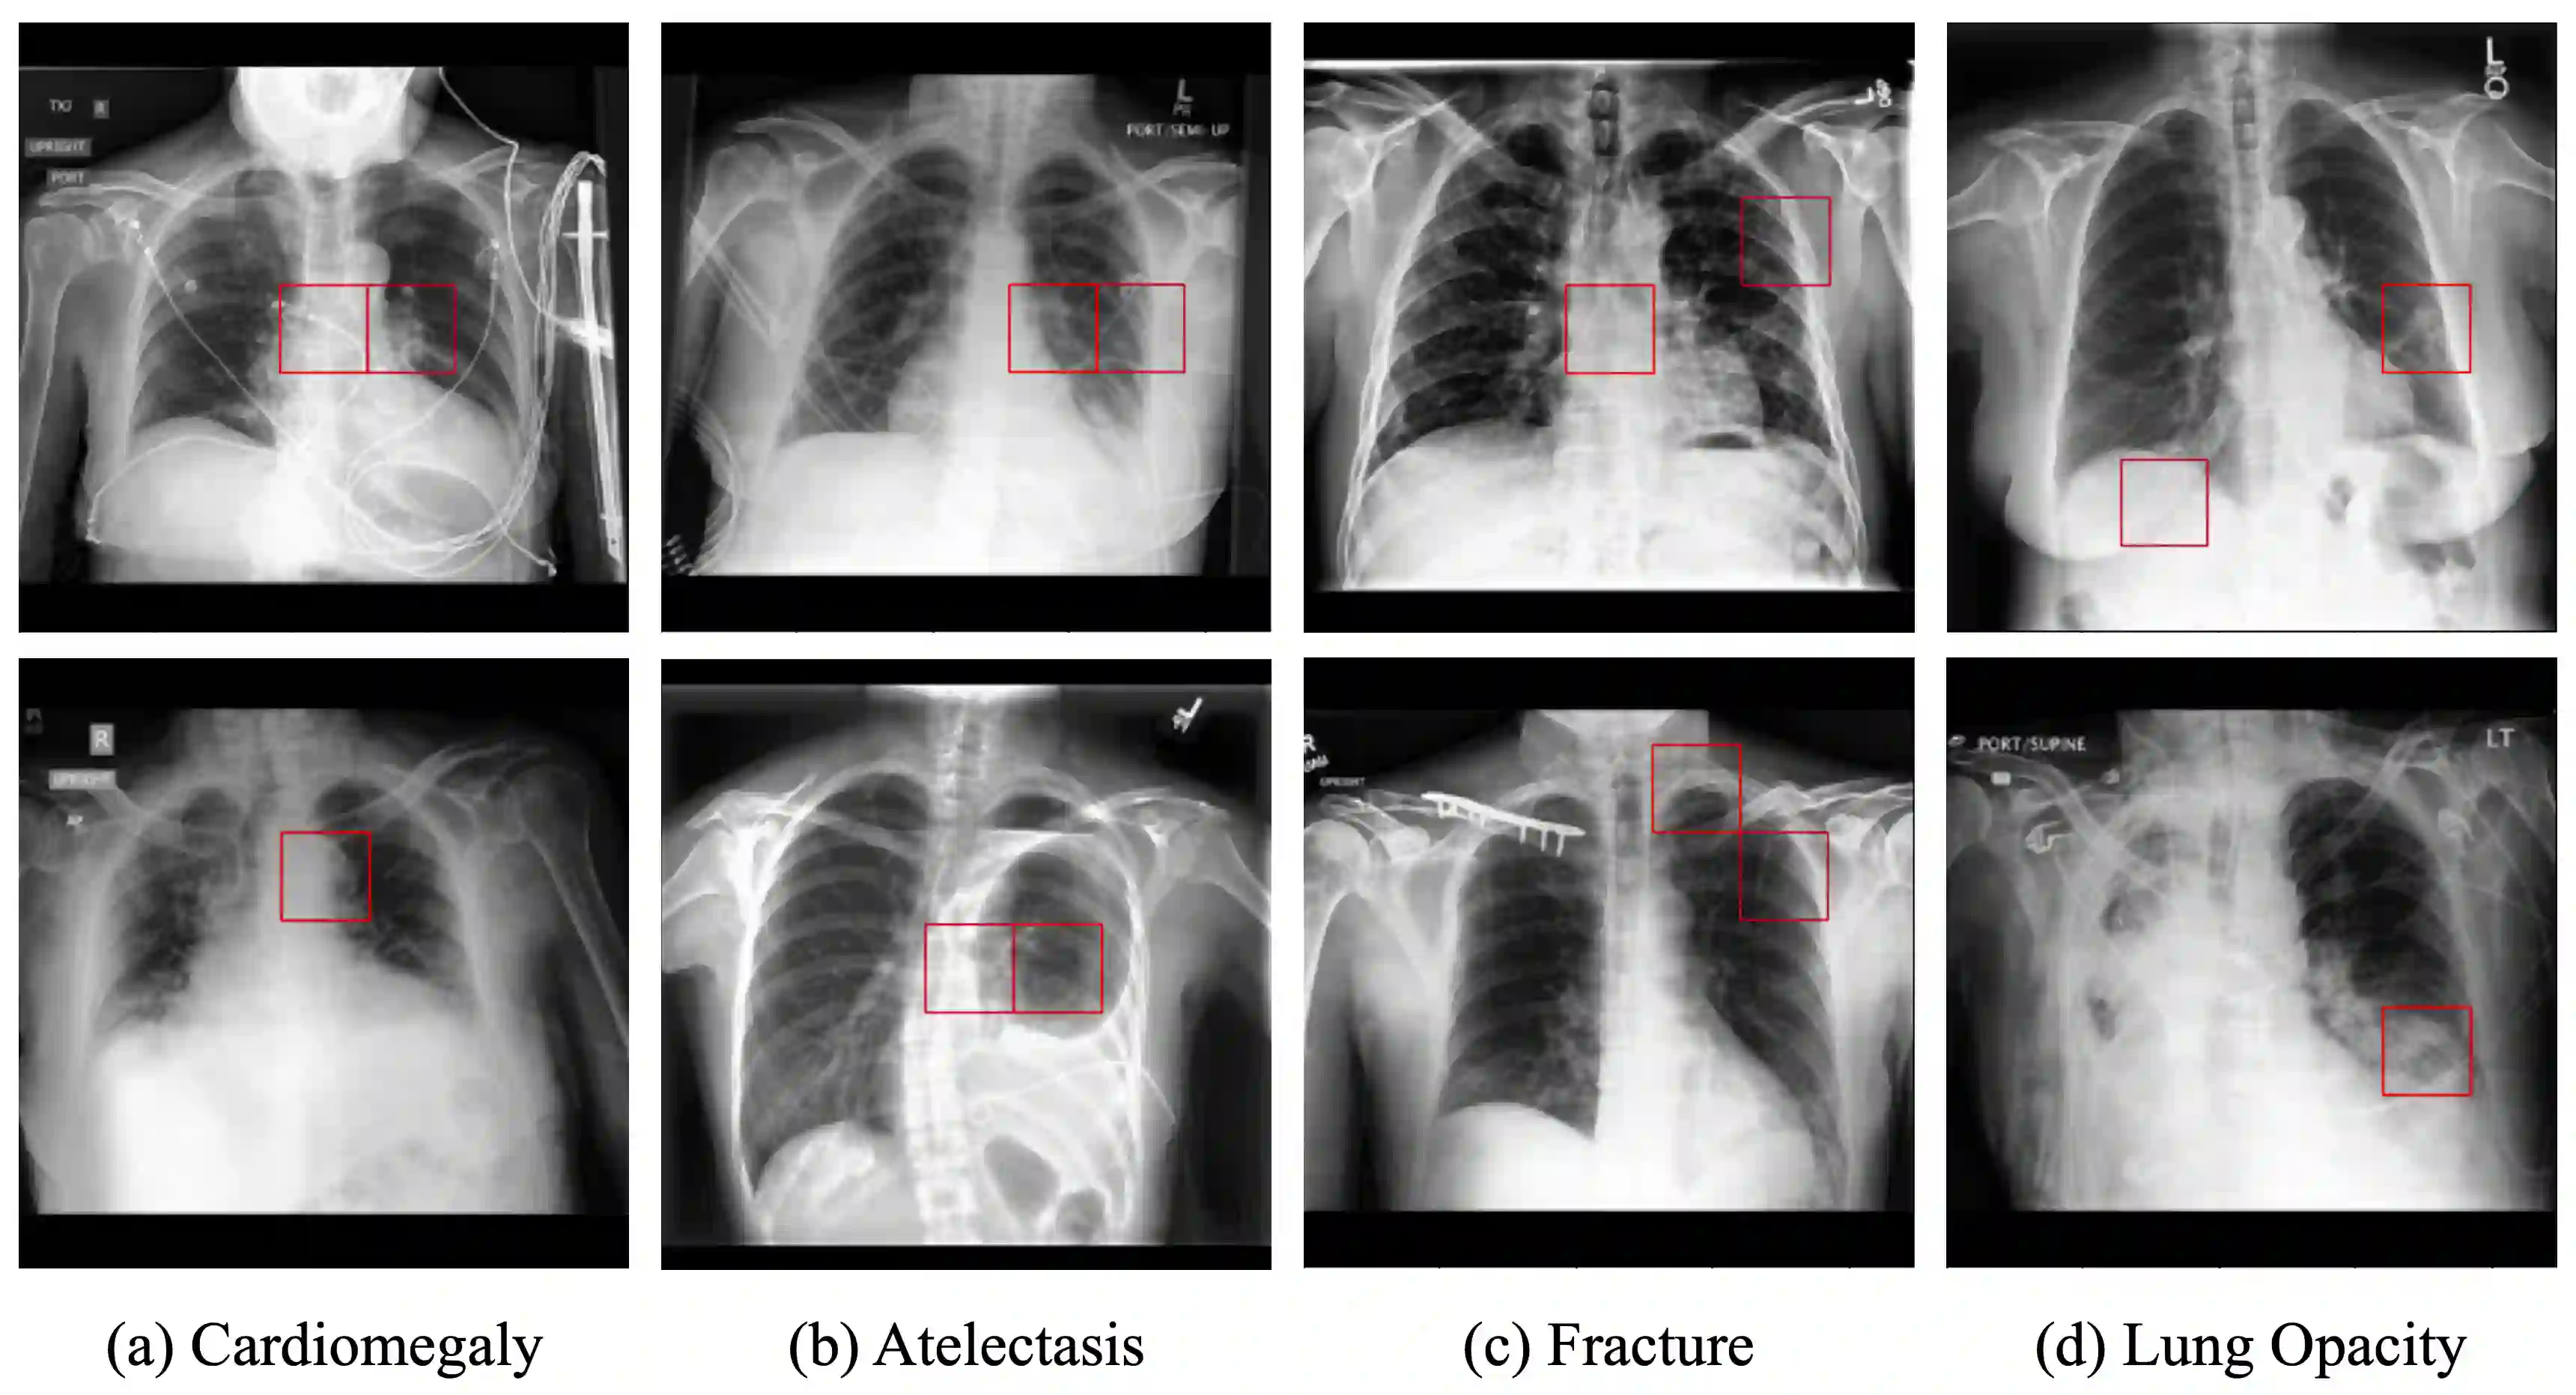

The proliferation of Deep Learning (DL)-based methods for radiographic image analysis has created a great demand for expert-labeled radiology data. Recent self-supervised frameworks have alleviated the need for expert labeling by obtaining supervision from associated radiology reports. These frameworks, however, struggle to distinguish the subtle differences between different pathologies in medical images. Additionally, many of them do not provide interpretation between image regions and text, making it difficult for radiologists to assess model predictions. In this work, we propose Local Region Contrastive Learning (LRCLR), a flexible fine-tuning framework that adds layers for significant image region selection as well as cross-modality interaction. Our results on an external validation set of chest x-rays suggest that LRCLR identifies significant local image regions and provides meaningful interpretation against radiology text while improving zero-shot performance on several chest x-ray medical findings.